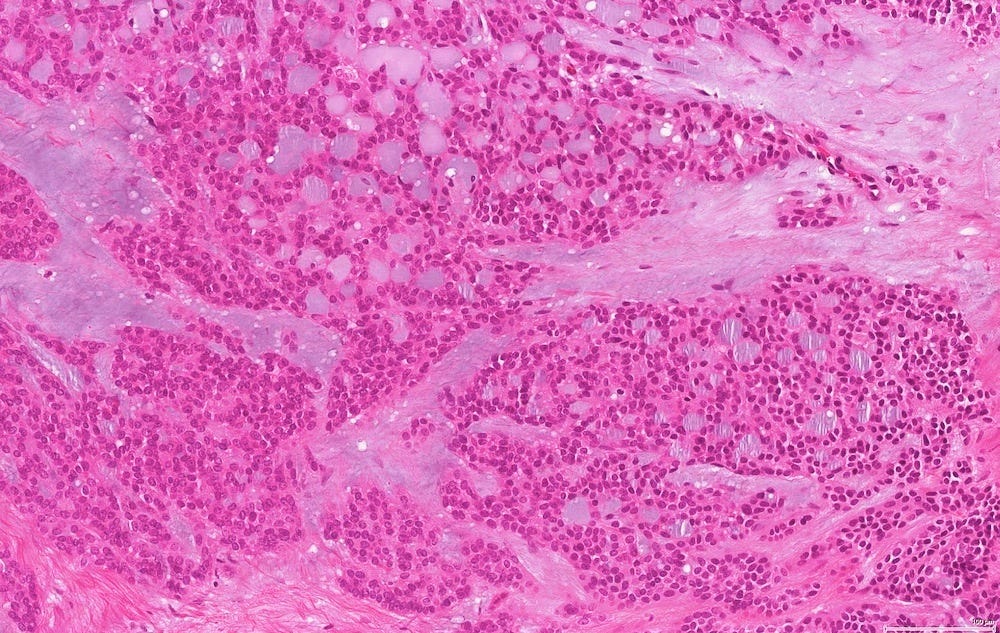

In reported cases, the tumor appears as a well circumscribed, firm mass. Microscopically, reported cases exhibited a wide spectrum of growth patterns, including solid nests, trabeculae, tubules, cribriform structures, strands and fascicles. In these cases, the tumor cells were monotonous with uniform nuclei and scant cytoplasm, lacking significant pleomorphism or mitotic activity.

Polymorphic carcinoma - microscopic images

Note: due to its rarity in the breast, these images are from the similar tumor in the salivary glands